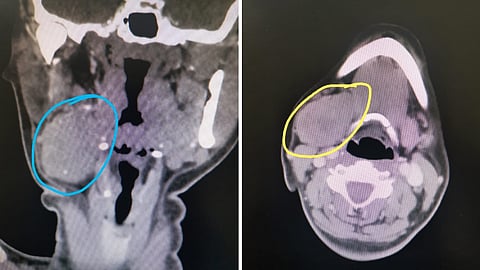

وأوضحت الفحوصات السريرية والإشعاعية التي أجريت للمريضة وجود كتلة تشمل الغدة بشكل كامل، ليتم لاحقاً اتخاذ الإجراءات الطبية اللازمة واستكمال التحاليل والتقييمات تمهيداً للعملية.

أُجريت العملية تحت التخدير العام، وتمكن الفريق الجراحي من استئصال الورم بالكامل خلال نحو ساعتين دون التسبب بأي إصابة في فروع العصب الوجهي، ودون ظهور علامات تجمع للعاب (سِيالوُسيل)، ما يُعد مؤشراً على الدقة العالية في الأداء الجراحي.

وأُرسلت العينة المستأصلة إلى قسم الأنسجة المرضية، والذي أكد أن الورم من نوع الورم الغدي متعدد الأشكال (Pleomorphic Adenoma)، وهو ورم حميد بطبيعته، مما طمأن المريضة وأسرتها.